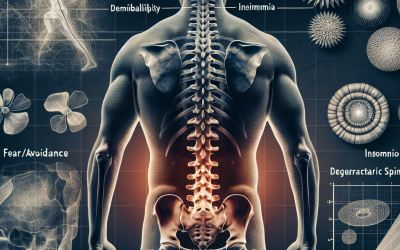

Relación entre la morfometría multifidus lumbar y el dolor/discapacidad en individuos con dolor lumbar no específico crónico después de considerar la demografía, las creencias de evasión del miedo, el insomnio y los cambios degenerativos espinales

Resumen Antecedentes: Aunque las personas con dolor lumbar crónico (CLBP) muestran una mayor infiltración de grasa en el músculo multifidus lumbar (LMM), no está claro si los cambios de LMM están relacionados con los resultados clínicos (como el dolor y la...